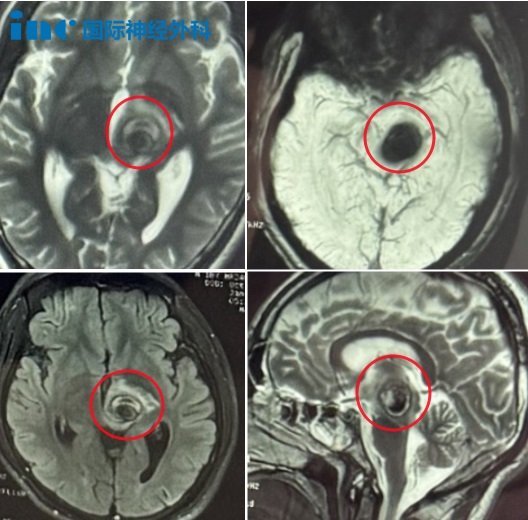

▼2023年6月23日,小林第1次出血

小林母亲每每回想起孩子第一次出血的情景,医生的话就像一声晴天霹雳,顿时让他们心情沉重、如坠深渊。“当时孩子有点头疼头晕,脸有点麻,核磁查出来了。医生就说可能是一个海绵状血管瘤。后来我们又到了北京,医生看了一下,说这个没法动手术的。只要动是90%以上会瘫痪。别说90%,50%我也不敢让他动,因为孩子才18岁。没办法,回来之后就是保守治疗。”

▼2024年1月7日,小林第2次出血

第2次出血更是让小林母亲后怕不已:“保守观察到2024年1月份,头疼头晕再次出血,因为那段时间他总是熬夜凌晨。医生说治不了,在ICU待了几天也没有动手术。”

然而,此时,小林右侧胳膊出现明显麻木,腿部无力,不能行走。